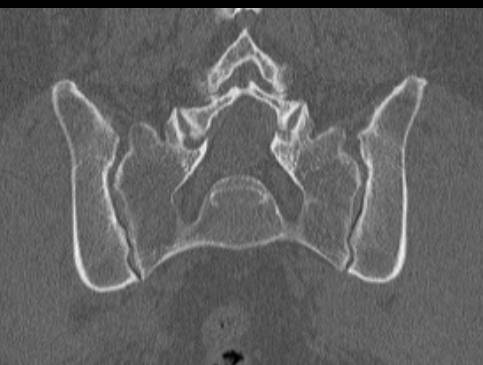

- сужение суставной щели (в норме она составляет 4-5 мм);

- на начальных стадиях заболевания возможно расширение суставной щели;

- на поздних стадиях патологии суставная щель полностью исчезает (полный анкилоз) или на КТ определяются «мостики» из соединительной ткани между суставными поверхностями (частичный анкилоз);

- уплотнение субхондральной (подхрящевой) кости, которое обычно сильнее выражено со стороны подвздошной кости, чем крестца;

- появление кист в субхондральной кости;

- эрозии на суставных поверхностях.